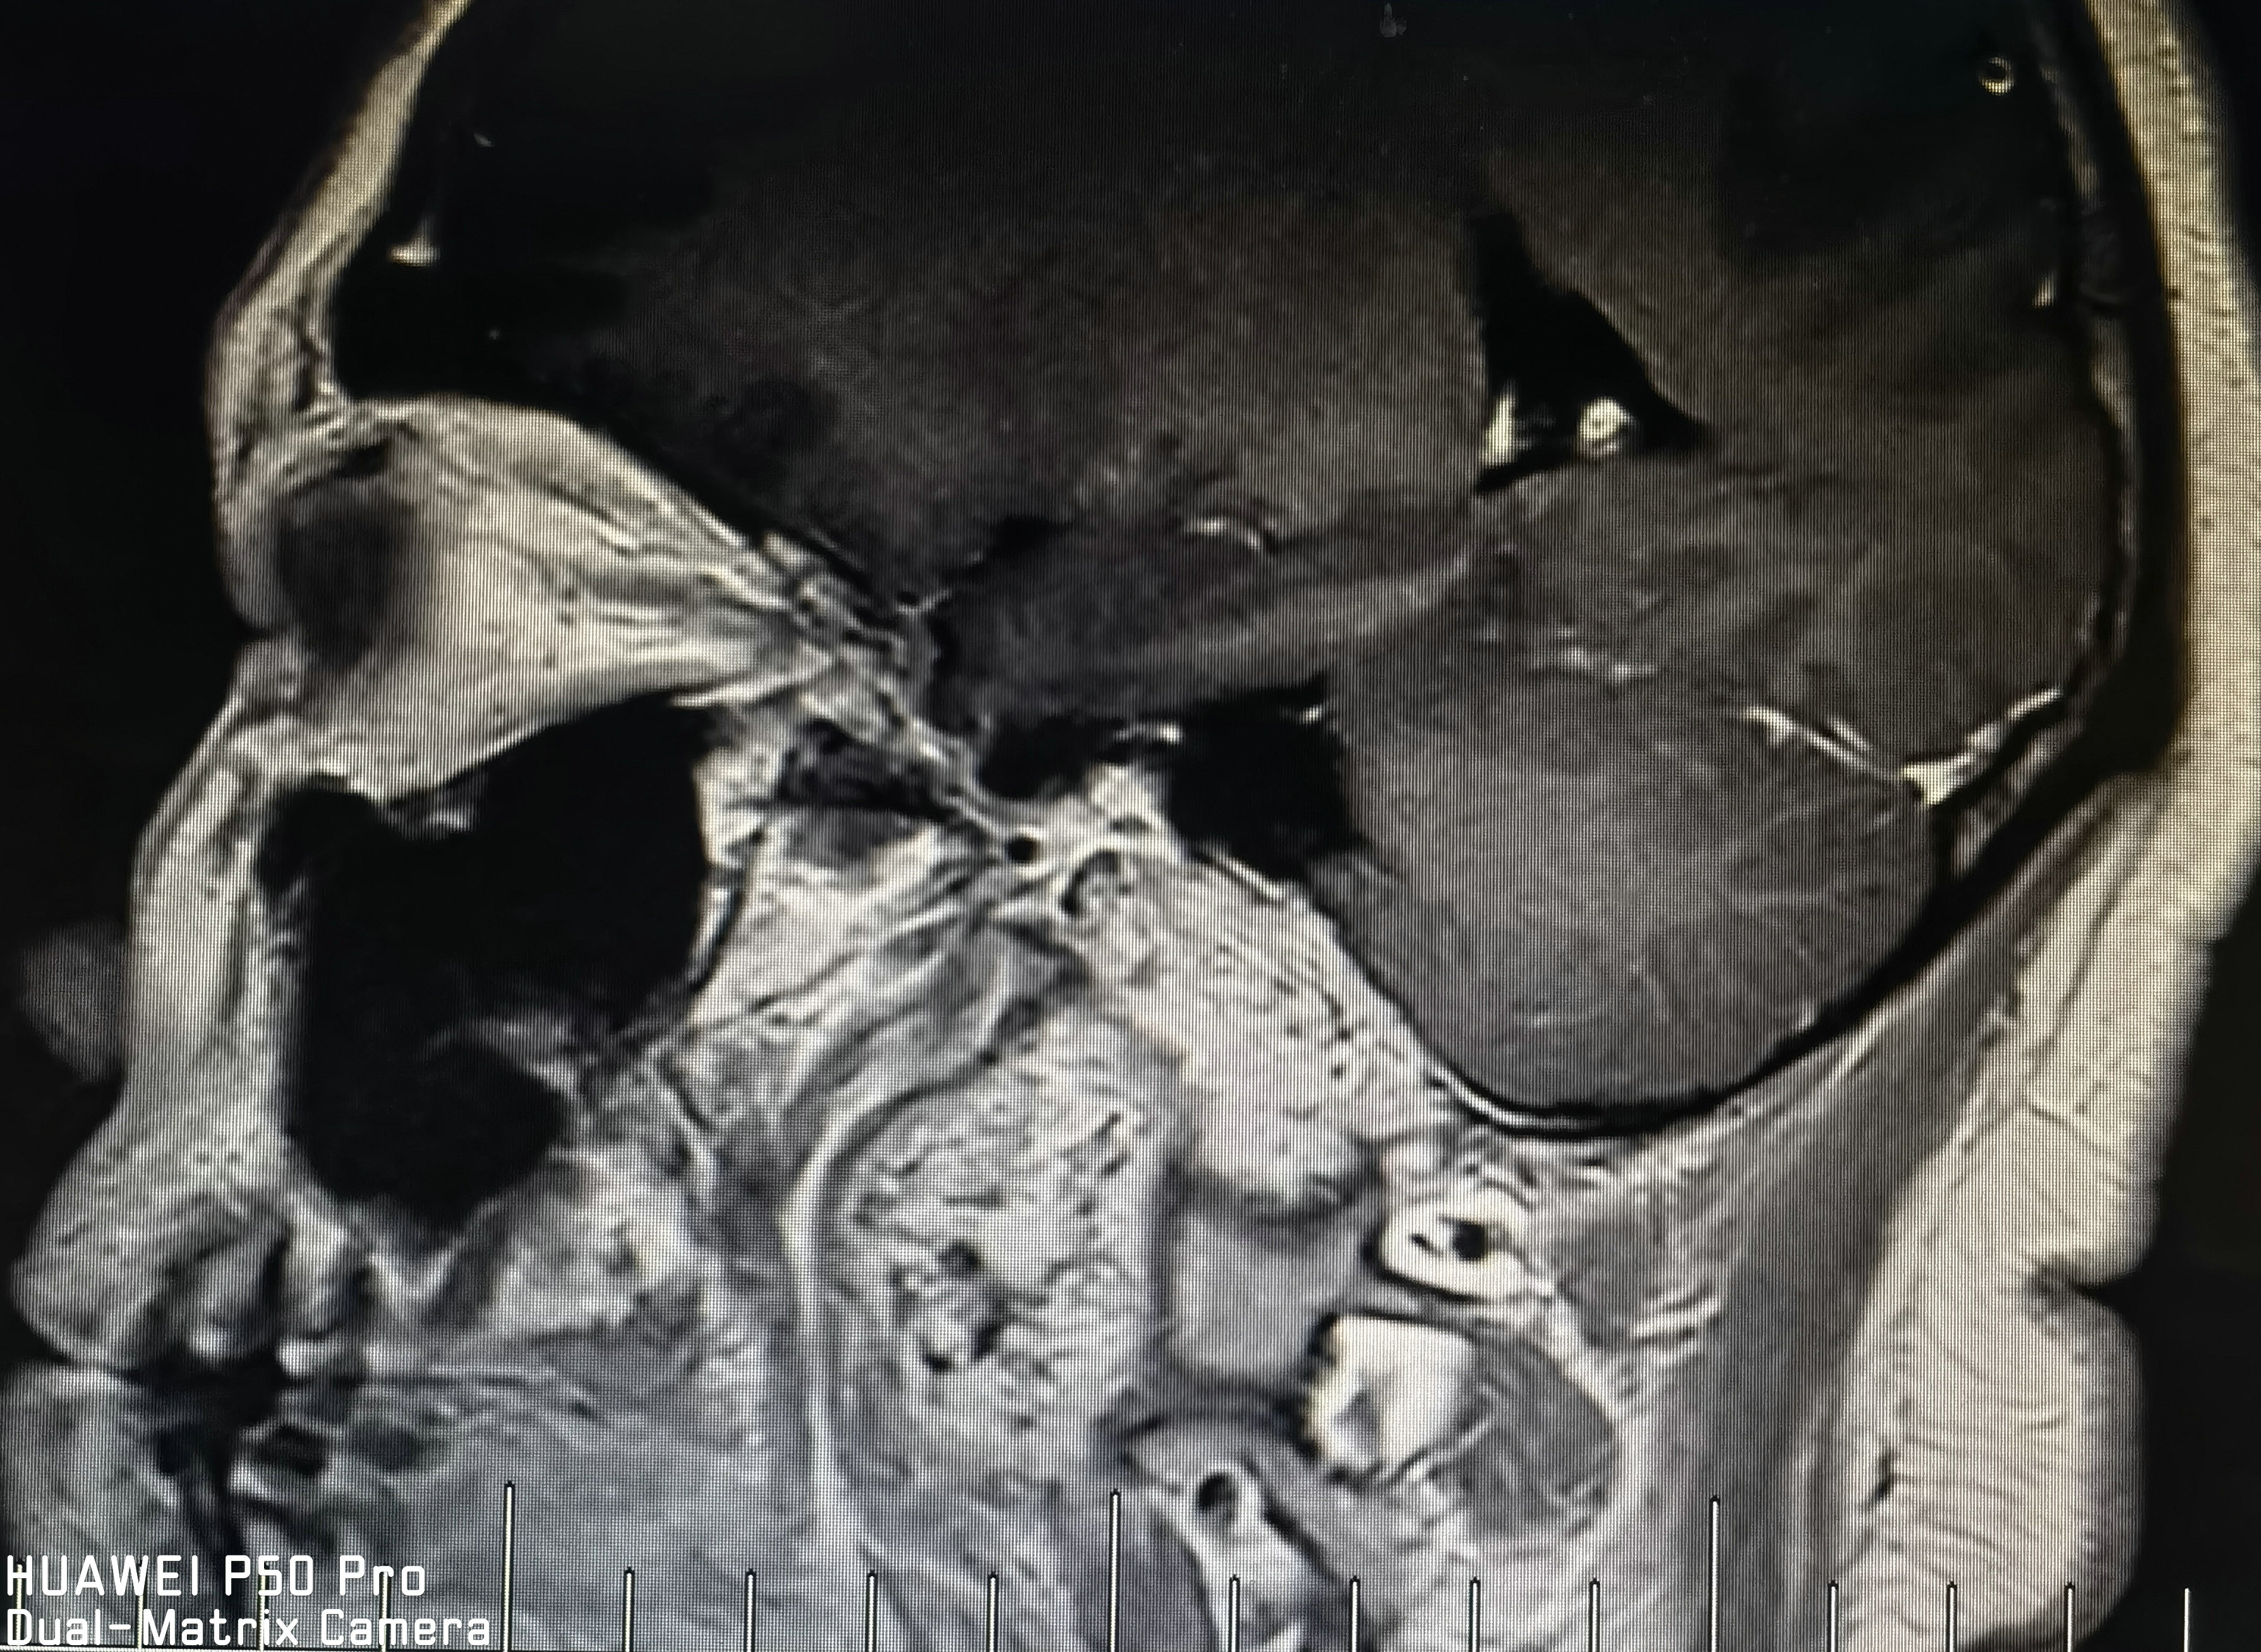

术前磁共振